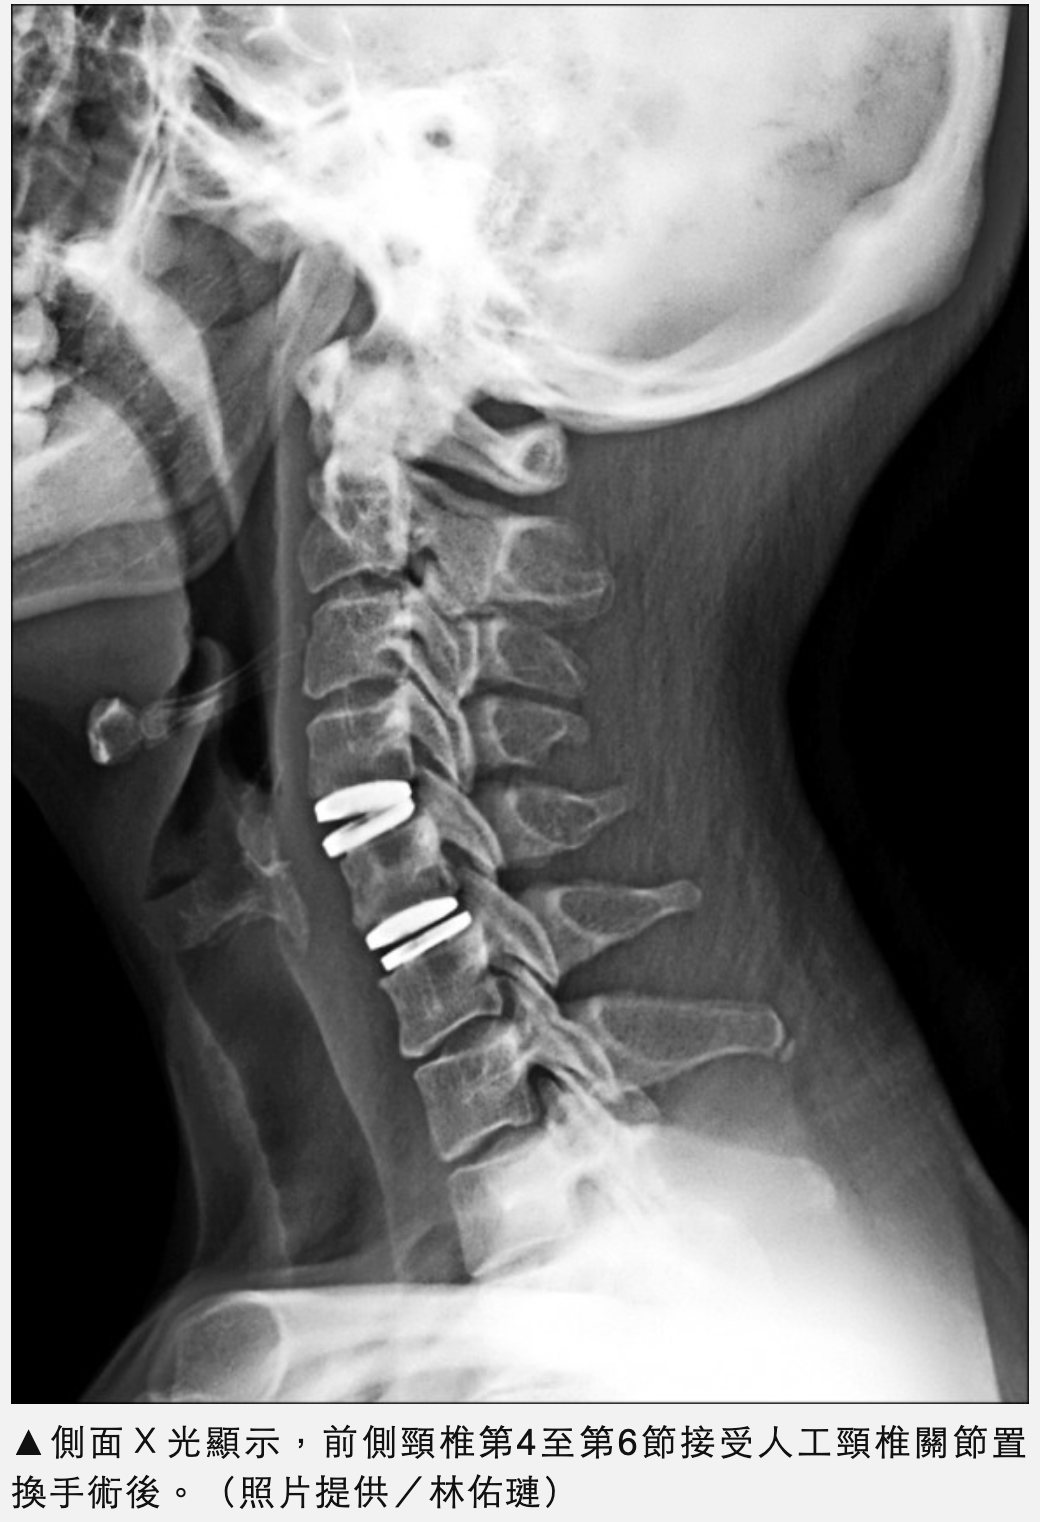

置換人工頸椎間盤 工程師24小時出院3天上班

一名36歲台積電工程師因長期於無塵室操作電機配備及電腦,右側持續性的肩膀及右前臂痠麻,更惡化到右手無力。檢查後是頸椎第4節至第6節椎間盤突出造成第4節至第6節右側神經根以及脊隨壓迫。在接受微創頸椎第4...